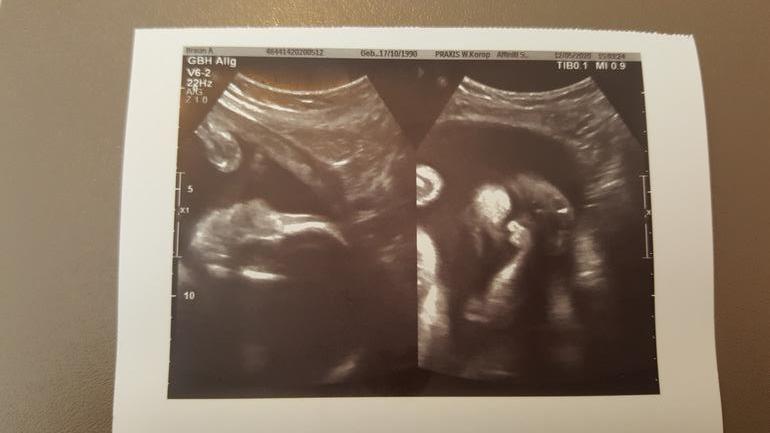

Сделали нам сегодня скрининг в 28+4 недели. И как всегда у меня море эмоций)) Ну такая сладенькая, но и вредненькая, девочка у меня там. Лежит головкой вниз и достаёт до шейки😒 (на выход что ли готовится?) Зевала, воды глотала, чего-то губками шевелила. Пытались найти удачное 3Д фото, она лежала прикрыв одну сторону лица рукой, а потом вообще обеими закрылась😊

Вес примерно 1029гр и примерно 32см рост.